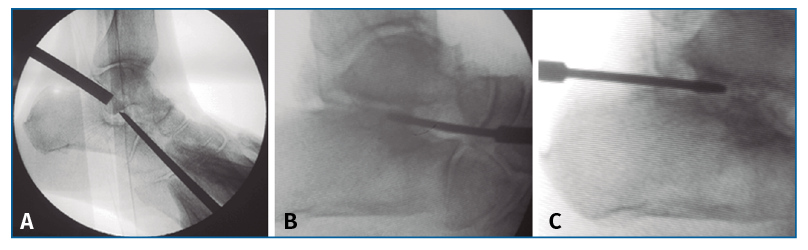

En segundo lugar, se aborda la articulación ST como indican Carranza et al.(30), se penetra la ST anterior y media por una incisión solo cutánea de 1 cm sobre el seno del tarso y la ST posterior por un portal posterolateral justo lateral al tendón de Aquiles, similar al portal artroscópico posterolateral descrito por van Dijk(31). Por estos 2 portales, finalmente se cruenta la articulación bajo control fluoroscópico hasta tejido subcondral con escoplos y brocas motorizadas (Figura 2).

Figura 2. Cruentación de la articulación subastragalina, bajo control fluoroscópico, hasta tejido subcondral, con escoplos (A) y brocas motorizadas (B y C).